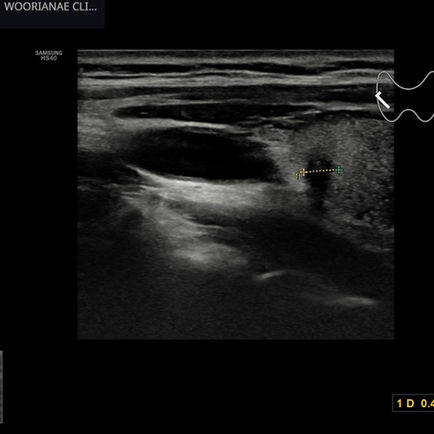

하복부, 골반 초음파; 난소종양

19시간 전

1분 분량